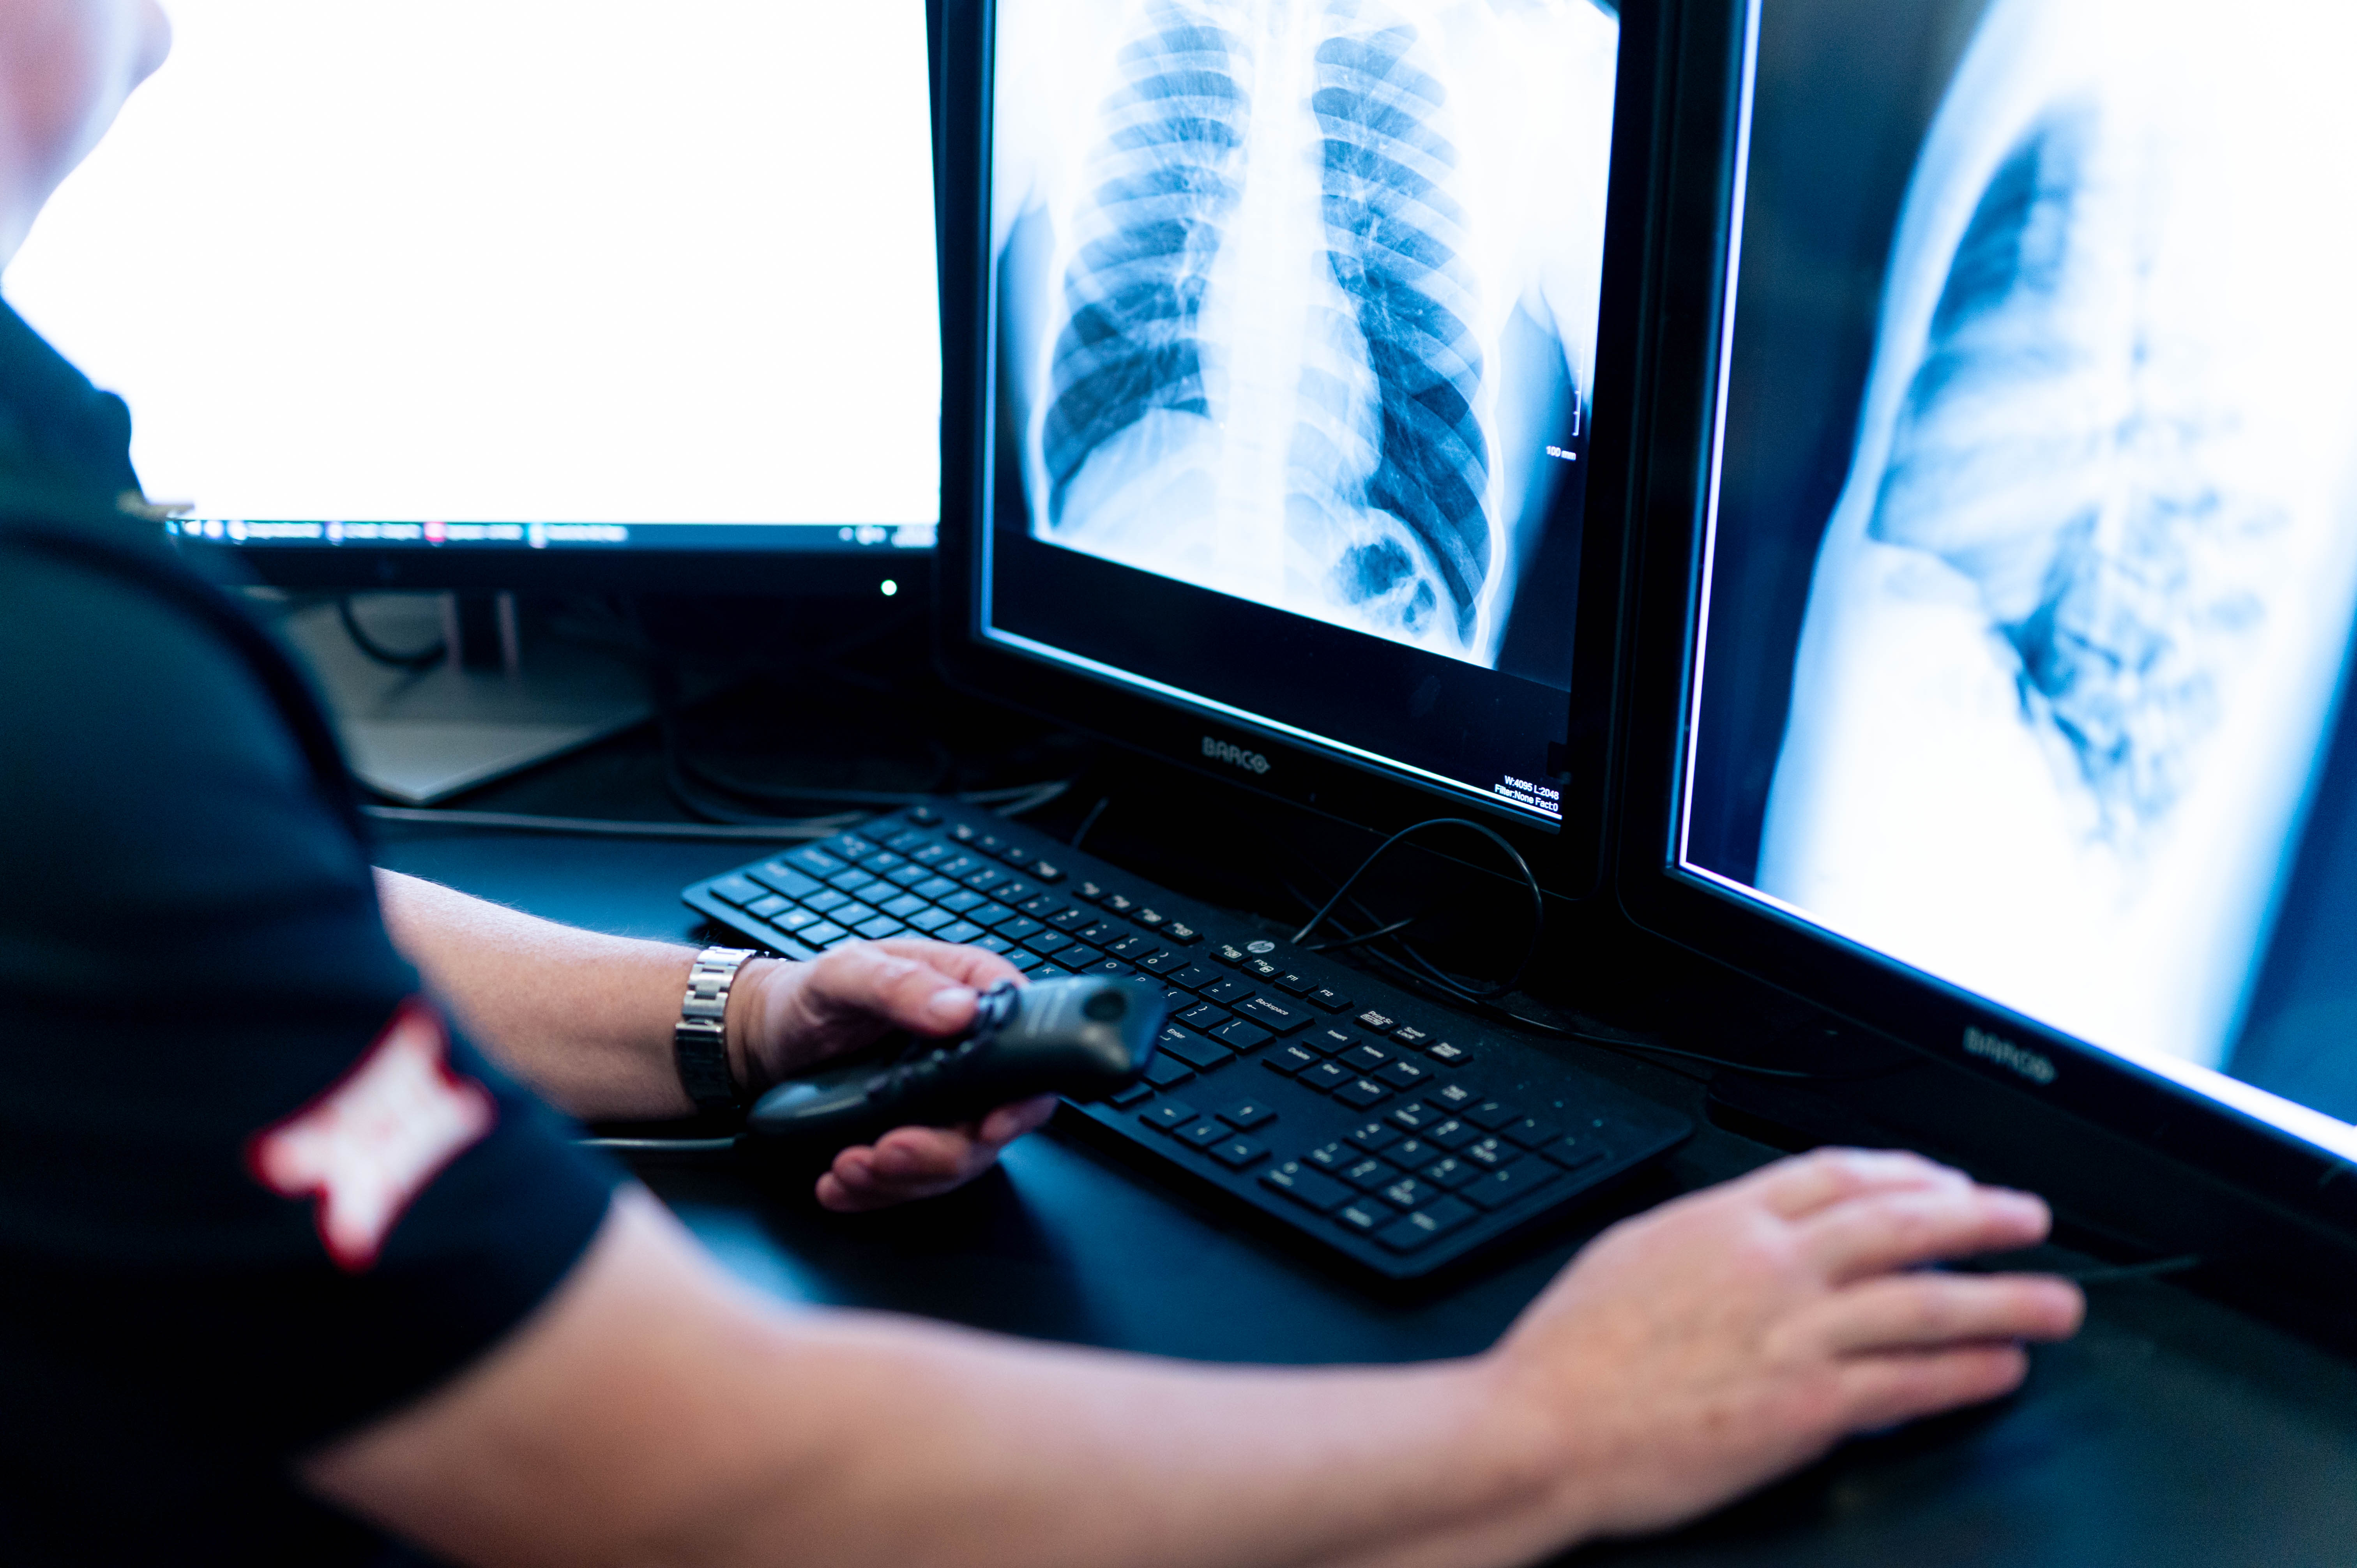

Our musculoskeletal radiology program collaborates closely with the sports medicine team at UC Health. Fellowship-trained radiologists, specialized imaging and shared expertise support athletes and active individuals in diagnosis, treatment and recovery. Our team’s approach aims for faster healing and safe return to activity.

At UC Health, fellowship-trained radiologists work side by side with specialists to deliver expert imaging, diagnosis and treatment—backed by research and commitment to your well-being.